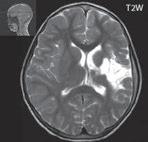

Obr. I.1.1f Rozšířené subarachnoidální prostory (věk 6 měsíců – v tomto období se nejedná o patologický stav, ale jsou fyziologicky prostornější)

Obr. I.1.1g Rozšířené subarachnoidální prostory (věk 6 měsíců – v tomto období se nejedná o patologický stav, ale jsou fyziologicky prostornější); stejný pacient jako na obr I 1 1f

f g h ch

Obr. I.1.1h Fyziologický nález, již normální šíře subarachnoidálních prostor (věk 1,5 roku); stejný pacient jako na obr I 1 1f, g

Obr. I.1.1ch Fyziologický nález, již normální šíře subarachnoidálních prostor (věk 1,5 roku); stejný pacient jako na obr I 1 1f, g, h